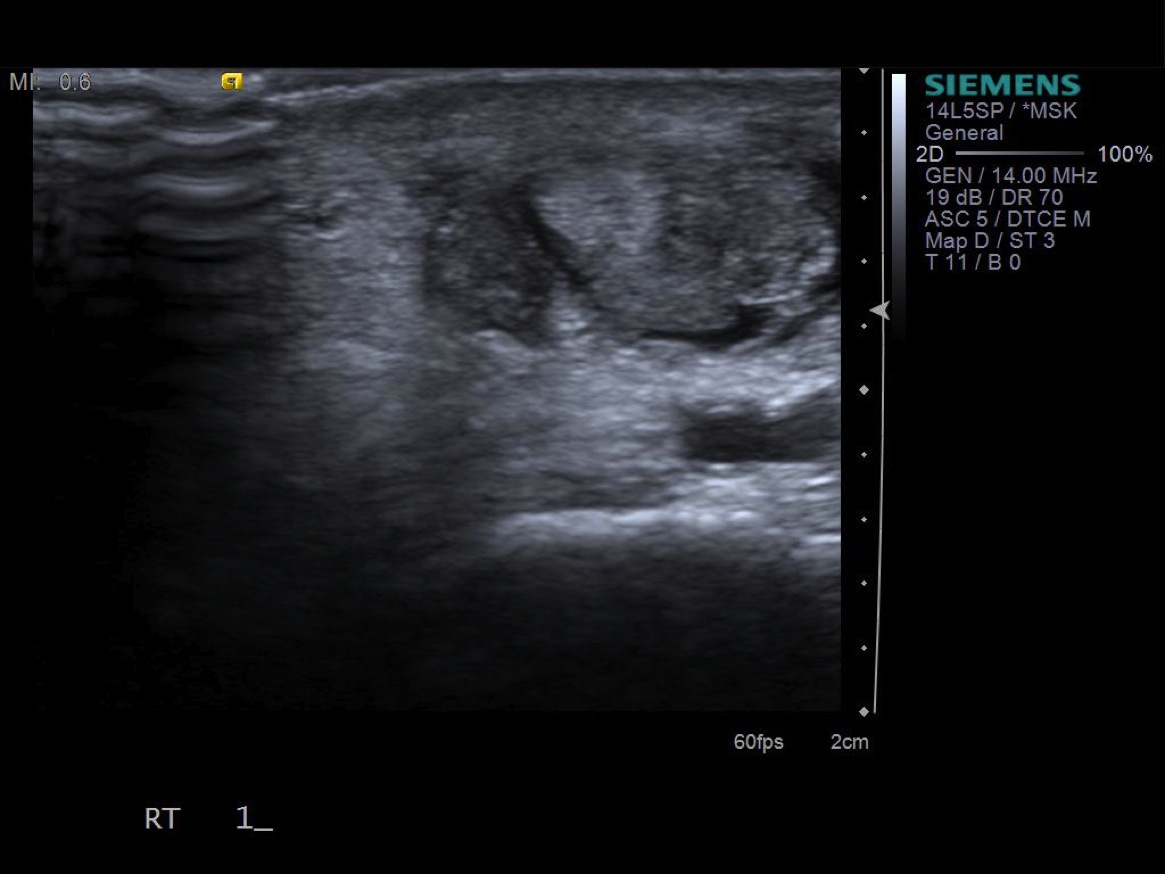

• probe: 14Mhz hockey stick probe

3. Place probe in short axis over first comparment extensor tendons-- Extensor pollicis brevis and abductor pollicis longus. description description